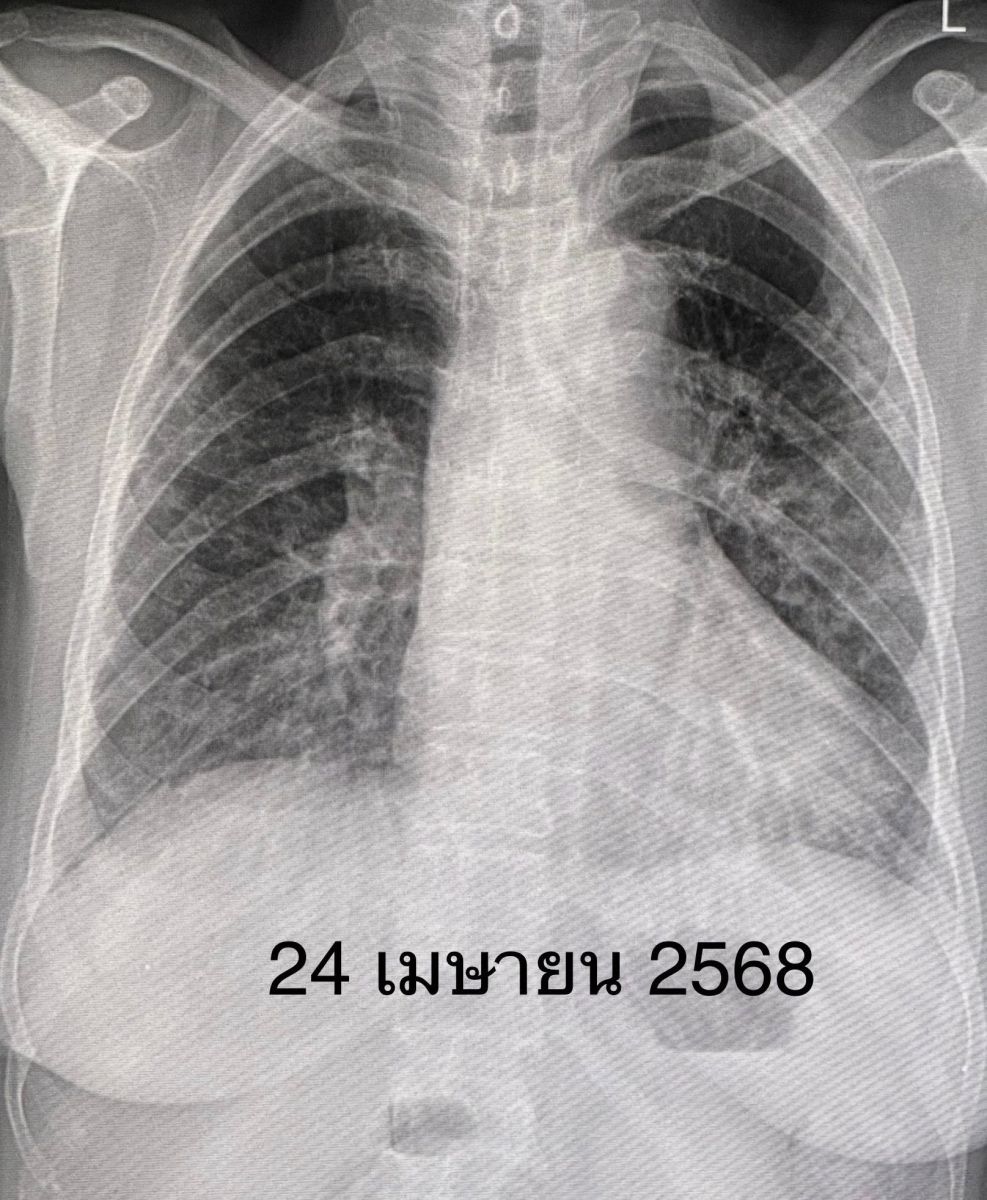

สรุปแล้วผู้ป่วยรายนี้เป็นโรคภูมิต้านทานตัวเองชนิด Anti-MDA5 antibody positive dermatomyositis ทำให้เนื้อเยื่อปอดอักเสบ และปอดเกิดพังผืดอย่างรวดเร็ว ไม่มีกล้ามเนื้ออ่อนแรง ไม่มีความผิดปกติของผิวหนัง ให้ยาสเตียรอยด์ชนิดฉีดขนาดสูง ต่อมาเปลี่ยนเป็นชนิดกิน ยากดภูมิคุ้มกันไมโคฟีโนเลต ยาไฮดรอกซีคลอโรควิน และยา Tolvaptan รักษาโรคโซเดียมในเลือดต่ำ

ทั้งนี้คนไข้คนดังกล่าวมีความเหนื่อยน้อยลง ระดับออกซิเจนที่ปลายนิ้วดีขึ้น ใช้ออกซิเจนแบบหนวดกุ้งธรรมดาทางจมูก ไม่ต้องใช้ High-Flow nasal O2 cannula เอกซเรย์ปอดดีขึ้นช้าๆ ลุกขึ้นเดินได้ ระดับโซเดียมในเลือดเกือบปกติ กลับบ้านได้หลังจากอยู่รพ. 15 วัน แต่ยังต้องมีการนัดติดตามคนไข้ต่อไป”